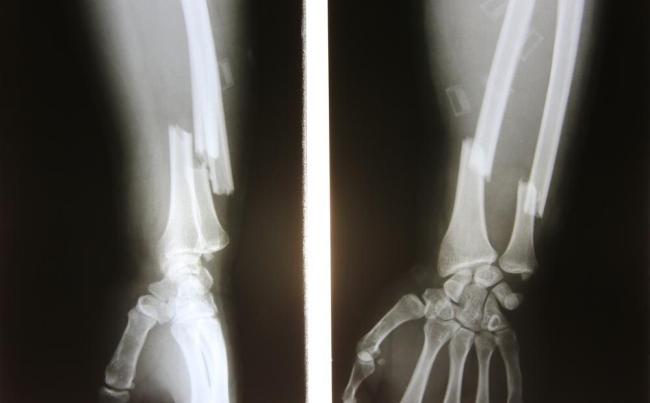

Bệnh cơ xương khớp

Càng nhiều tuổi, hệ cơ xương khớp càng trải qua quá trình hao mòn nhất định, gây đau khớp, đau lưng cũng như các chấn thương cơ xương khớp khác, làm ảnh hưởng hoặc hạn chế khả năng vận động. Cùng tìm hiểu thêm về những tình trạng sức khỏe có thể tác động đến hệ thống cơ xương khớp của bạn ngay tại đây.